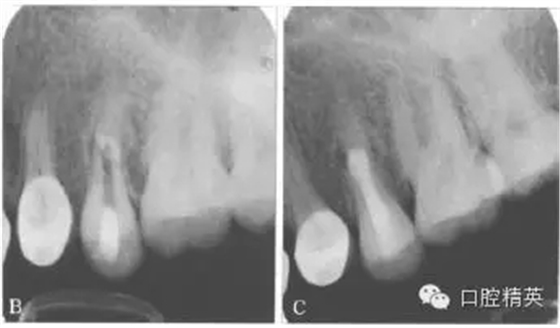

根管內(nèi)封vitapex糊劑1個(gè)月。第2次復(fù)診時(shí)瘺管已經(jīng)消退,顯微鏡下見根管內(nèi)斷端創(chuàng)面為肉芽組織,斷端直徑約為3 mm×3 mm,采用MTA連接斷端(圖4左),置生理鹽水小棉捻,氧化鋅暫封。3 d后MTA已硬化,注射熱牙膠封閉根管上段,樹脂修復(fù),降低咬合(圖4右)。

圖4 X線片。左:MTA連接斷端;右:充填片;